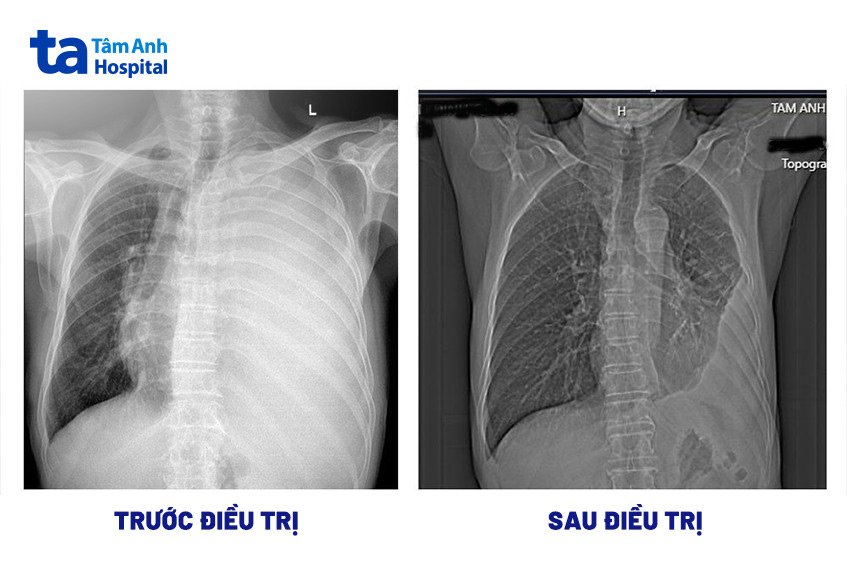

Chụp X-quang ngực có thể là tất cả những gì cần thiết để chẩn đoán xẹp phổi. Nhưng các xét nghiệm khác có thể được thực hiện để xác định nguồn gốc của các triệu chứng hoặc tìm ra mức độ nghiêm trọng của xẹp phổi.